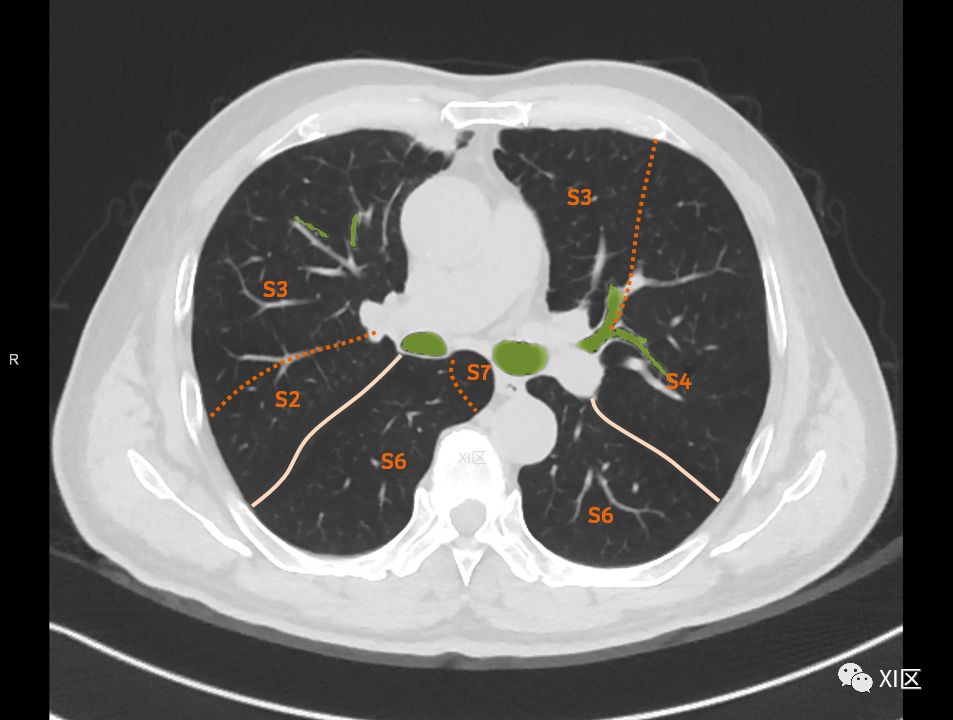

在进行肺的分段时,可以上下观察浏览,沿着相应气管的走形可以更容易准确地进行分段。

肺的分段

肺的断层分段示意图